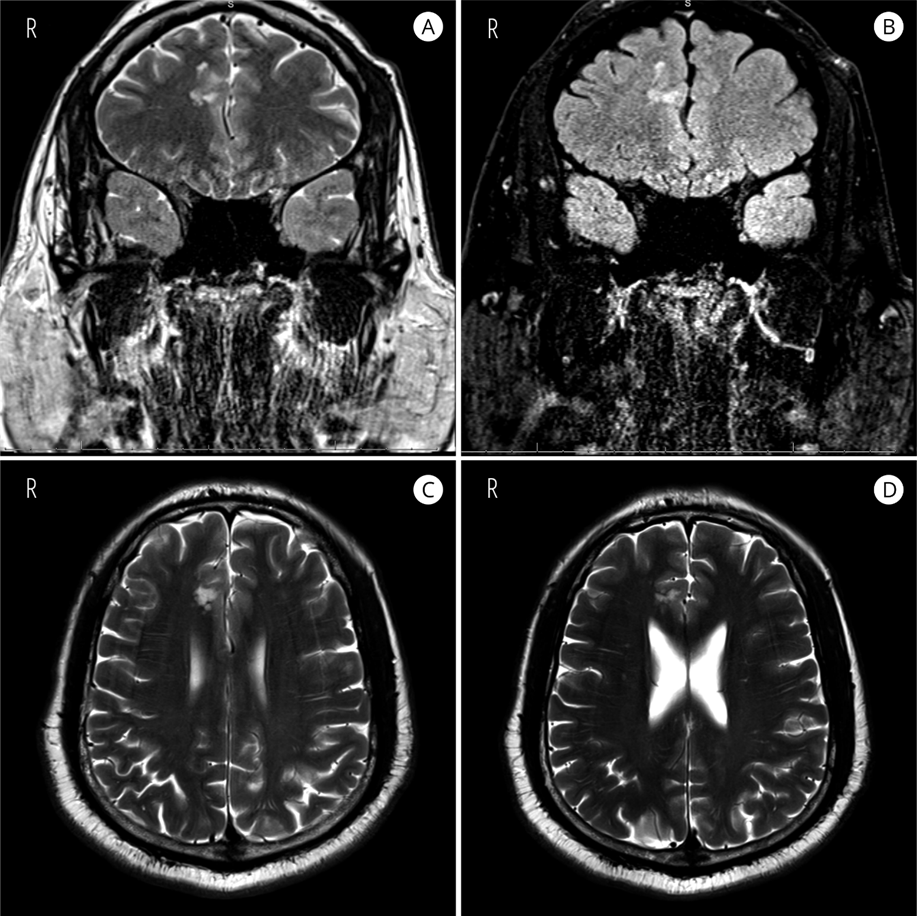

Clinical History: A 53-year-old male with a history of intractable epilepsy since adolescence presented for evaluation. MRI revealed nodular, non-enhancing subcortical T2/FLAIR hyperintense lesions in the right parasagittal frontal lobe, along the cingulate gyrus and sulcus, measuring 18 x 13.2 x 12.8 mm in aggregate. The patient underwent complete surgical resection and became seizure-free postoperatively with tapering of antiepileptic medications.

MRI: Multiple hyperintense nodules in the right parasagittal frontal lobe on T2 (A, C, and D) and T2 FLAIR (B).